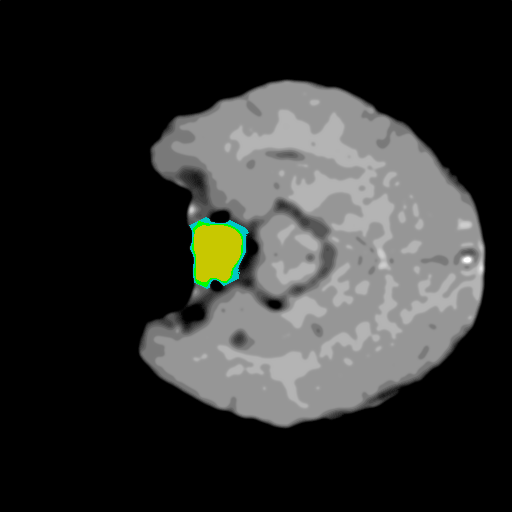

Extensive experiments have been performed in the current setup, and experimental outcomes are reported with the demonstration of numerical and statistical analyses using the proposed QFS-Net, QIS-Net [39], convolutional U-Net [18] and Residual U-Net (URes-Net) architectures [20]. The human expert segmented skull-tripped contrast enhanced DSC brain MR input image slices of size and ROIs are provided in Figure 5 as samples. The demonstration of QFS-Net segmented images followed by the essential post-processed outcome on the slice no. for class level with four distinct activation schemes () are shown in Figure 6. It is evident from the experimental data provided in Table LABEL:tab1 that the proposed QFS-Net performs optimally for the -connected quantum fuzzy pixel information heterogeneity assisted activation () with and gray scale set in comparison with other thresholding schemes and gray scale sets under the four evaluation parameters () [44]. The segmented tumors obtained using the proposed self-supervised procedure under class transition levels with four different thresholding schemes , , and are demonstrated in Figures 7- 8 for the class boundary sets and [39], respectively. The segmented images using the remaining two class boundary sets ( and ) [39] are provided in the supplementary materials section. The segmented ROIs describing the whole tumor region after the masking procedure using QIS-Net, U-Net and URes-Net are also reported in Figure 9.